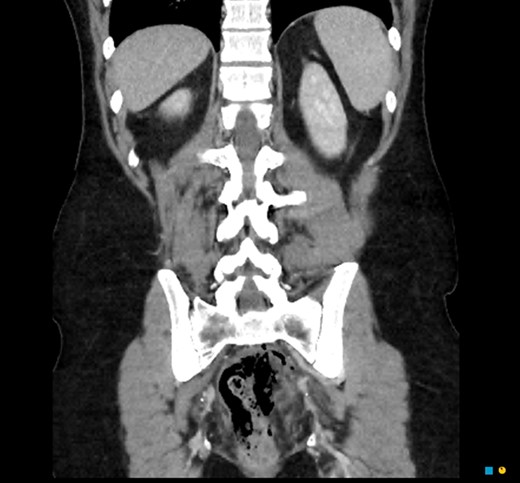

In the regional hospital, the patient had progressive peritonitis and vomiting. He was tachycardic and febrile (Temp 38.5°C). His initial work up demonstrated urea 11.9 mmol/l, creatinine 121 umol/l, C-reactive protein 201 mg/l, white cell count 30.7 × 109/l and haemoglobin 112 g/l. An urgent CT abdomen and pelvis demonstrated a large amount of free gas in the perirectal space consistent with a rectal perforation (Figs 1–3). The rectum itself was thick-walled and oedematous, as well as the sigmoid colon. He was transferred to the referral Tertiary hospital where an urgent laparotomy was performed.

CT coronal. Pneumointestinalis of the rectum suggestive of perforation.